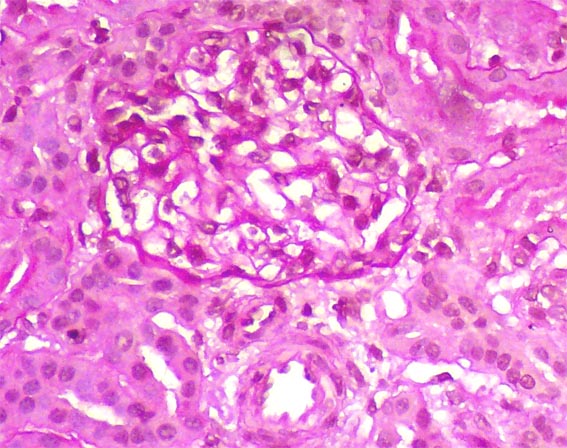

The patient is a 4-year-old girl who presented nephrotic syndrome in the first year of life, with biopsy in which focal segmental glomerulosclerosis was diagnosed. There was no response to multiple treatments. Molecular studies were unable to detect a specific genetic alteration. He developed ESRD at 3 years of age. She was in hemodialysis few months and was transplanted from a dead donor. Nephrectomy of a native kidney was done. Before the transplant, on dialysis, she had low urine output and non-nephrotic proteinuria without hypoalbuminemia or dyslipidemia. After transplantation presented progressive increase in proteinuria. Four post-transplant weeks there was complete nephrotic syndrome with proteinuria >100 mg/m2/h, dyslipidemia and hypoalbuminemia. Serum creatinine 0.5 mg/dL.

A renal biopsy was done, see the images.

Figure 4. H&E, X400.

Direct immunofluorescence for IgA, IgG, IgM, C3 and C1q: Negative. Immunohistochemistry for C4d: Negative.